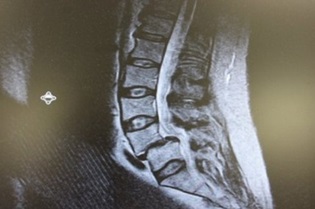

Методы визуализации позволяют поставить точный диагноз спондилолистеза и определить степень листеза, что очень важно для выбора тактики лечения.

Рентгенография позволяет определить как наличие листеза, так и степень смещения позвонков.

КТ или МРТ-сканирование могут более четко выявлять наличие повреждения дужек, а также исключить другие потенциальные патологии, такие как опухоли, инфекции или спинальный стеноз. Эти методы также позволяют определить наличие дегенерации в фасеточных суставах или дисках.